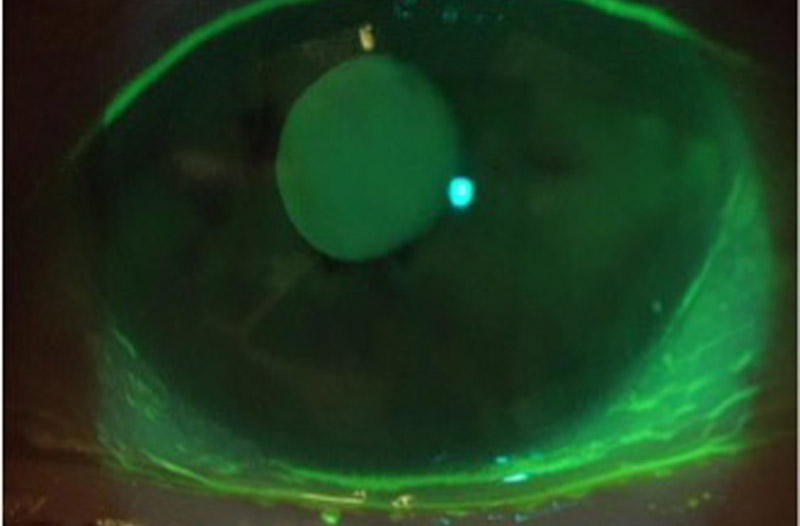

下瞼が内反して睫毛が眼球に当たっています。

黒目に傷ができて、異物感や涙目の原因となっています。

下瞼の向きが治り、睫毛が当たらなくなってい

ます。黒目の傷も治っています。